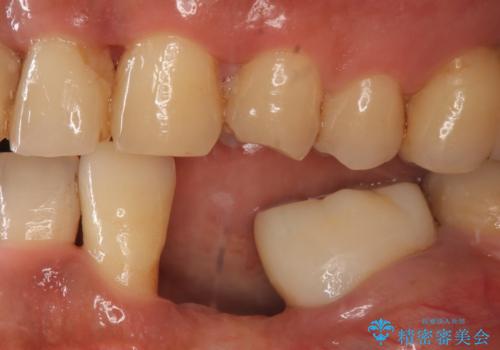

- 左下の歯並びが悪く、左側で物が咬みにくいので診て欲しいといらっしゃった方の症例です。

歯列矯正は御希望されなかったため左下4、5番目の歯を抜歯し、インプラントによる欠損補綴を行いました。

左下6も再根管治療後、オールセラミッククラウンによる補綴を行いました。